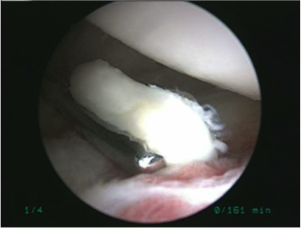

手術所見

| 遊離体 | 遊離体摘出時 |

| 前方関節唇損傷 | 損傷部位を縫合中 | 縫合終了 |